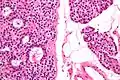

Микропрепарат аденомы паращитовидной железы.